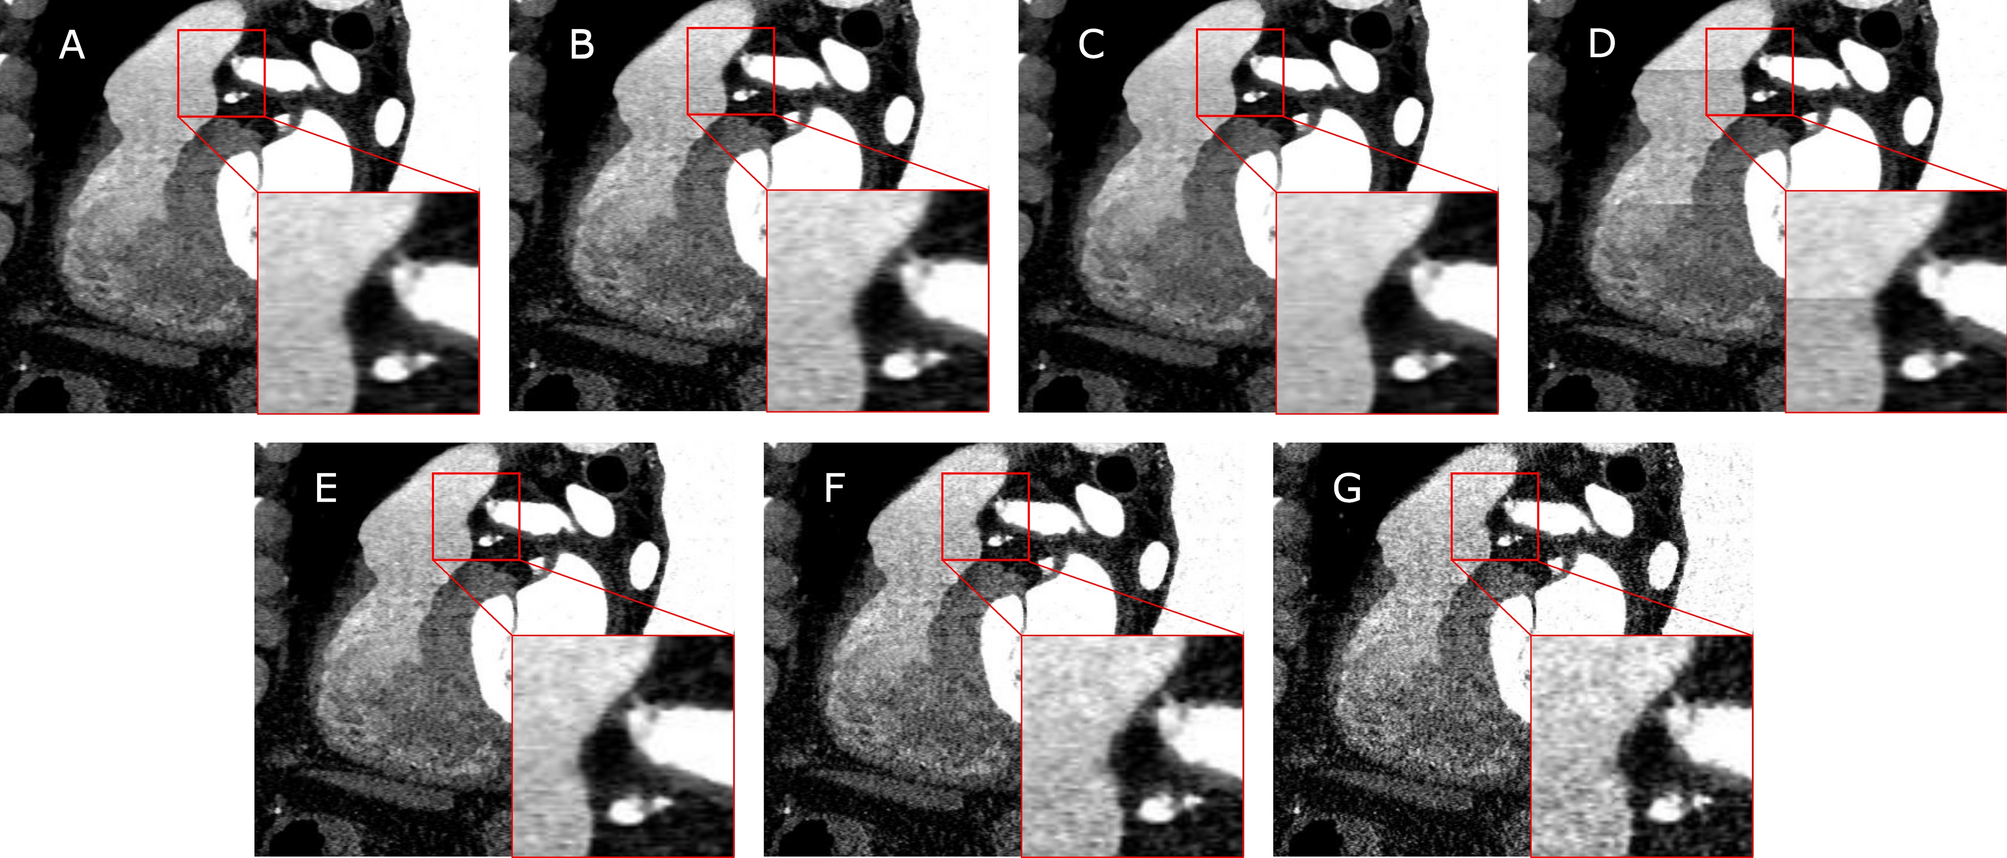

Figure 1

Sagittal views of a CCTA scan reconstructed with different parameters. The default configuration (A) reconstructed with an Advanced Modeled Iterative Reconstruction (ADMIRE) strength of 3, mixed stack and Bv36 kernel is varied by using: an ADMIRE strength of 2 (B) or 4 (C), using true stack (D) and utilizing a Bv40 (E), Bv44 (F) or Bv49 (G) reconstruction kernel.